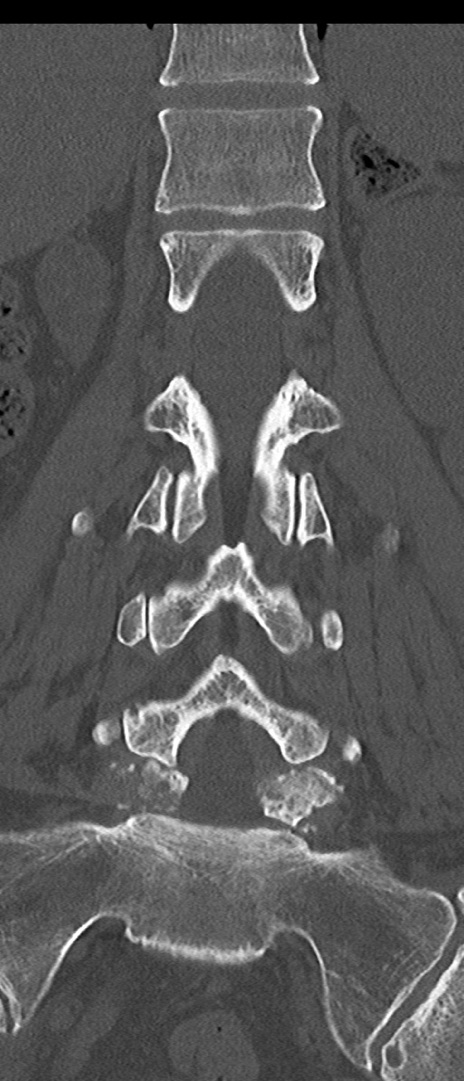

【整形】TIPS症例4 腰椎CT(冠状断像)

腰椎CT